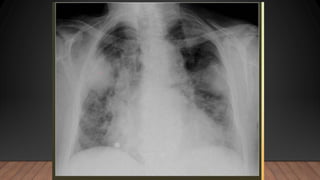

La neumonía causa un cuadro de condensación pulmonar producida por un exudado inflamatorio y proceso infeccioso que puede ser lobar, segmentario, intersticial, redondo o cavitario, siendo la forma lobar o alveolar la más común.